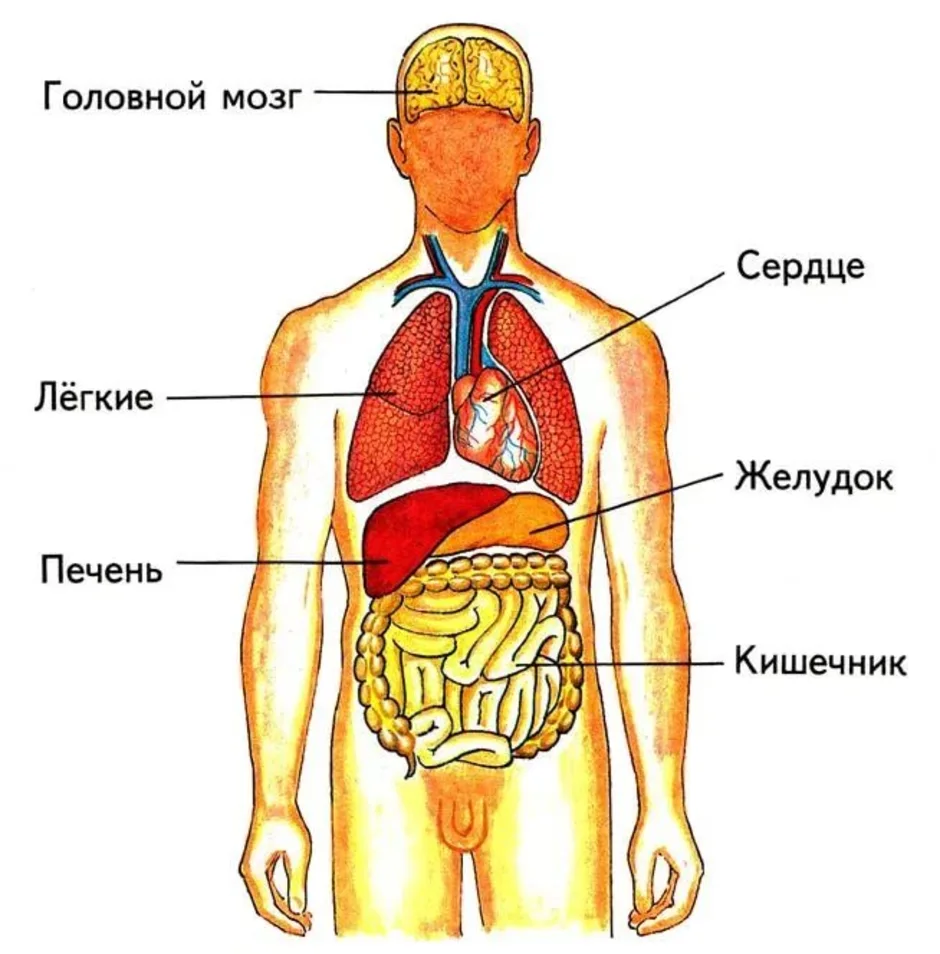

Анатомия желудка и сердца: визуализация и изучение

Раздел: Фотопанорама